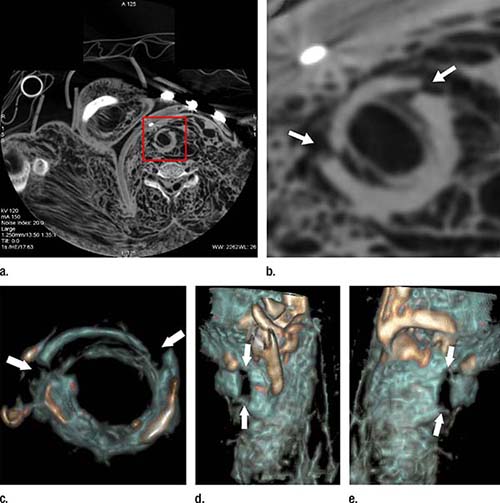

Modern imaging techniques like CT and MRI are often used in forensic pathology. However, post-mortem CT is limited by relatively low soft tissue contrast and poor visualization of the vascular system. A technique known as post-mortem CT angiography, or PMCTA, was developed to address those limitations by introducing contrast agent into the body.

“The idea of the PMCTA is to simulate a post-mortem circulation by establishing a post-mortem perfusion of the vascular system,” said study lead author Silke Grabherr, MD, PhD, from the University Center of Legal Medicine Lausanne-Geneva in Lausanne, Switzerland. “Therefore, the heart is ‘replaced’ by a perfusion device, similar to the heart-lung machine that replaces the heart during heart surgery.”

PMCTA was significantly superior to autopsy at identifying skeletal and vascular lesions, or areas of damage in the bones and blood vessels. PMCTA identified 96 percent of skeletal lesions and 94 percent of vascular lesions, compared with 65 percent for autopsy. These lesions can provide important information in post-mortem examinations, Dr. Grabherr said.

“The combination of bone lesions and vascular lesions is especially seen in cases of traumatic death, such as falls from height, traffic accidents, ballistic trauma and sharp trauma in homicides and suicides,” she said. “This means that PMCTA is an excellent choice to investigate such cases and can be used combined with or even independently of conventional autopsy for investigating in these cases.”